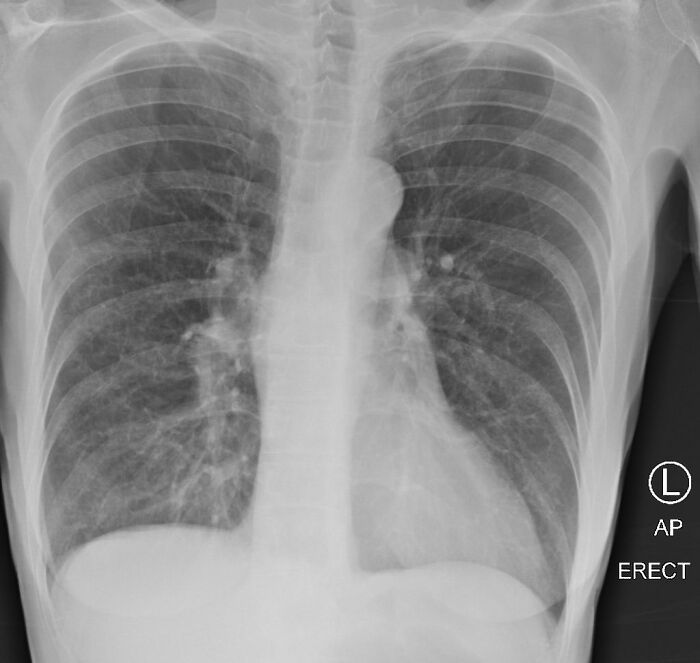

The doctor also posted photos of three lung X-rays—one of a healthy patient, one of a smoker, and one of a COVID-19 patient—to point out the differences.

Looking at the X-ray of a smoker’s lungs, you can notice some haziness indicating scarring and congestion